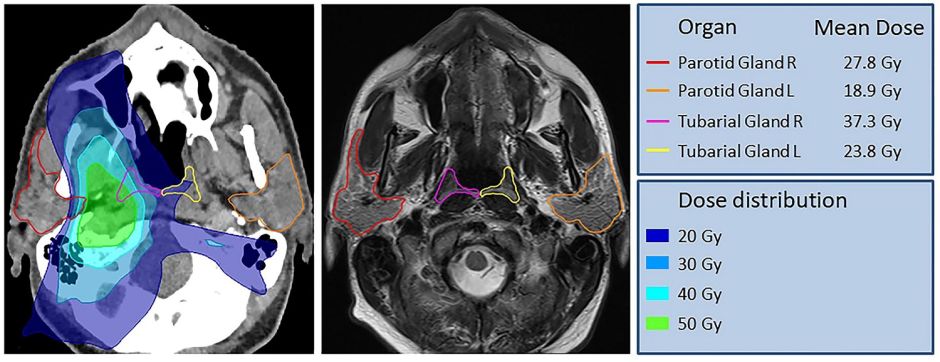

Las "nuevas" glándulas se ubican en la zona de la cavidad nasal y la garganta. Crédito: Radiotherapy & Oncology Journal | Cortesía

Se trata de unas glándulas salivales macroscópicas nasofaríngeas, es decir, que se encuentran ubicadas en el cráneo, en la zona de la cavidad nasal y la garganta. Mientras realizaban una investigación sobre el cáncer de próstata, los científicos descubrieron la presencia de estos órganos, que proponen llamar “glándulas tubarias”, al escanear la cabeza y el cuello de 100 personas, y al diseccionar un cadáver femenino y otro masculino.

Luego de realizar sus observaciones mediante tomografías computarizadas detalladas, los expertos llegaron a la conclusión de que “el cuerpo humano contiene un par de ubicaciones de glándulas salivales macroscópicas clínicamente relevantes y previamente pasadas por alto” que, de momento, han llamado glándulas tubarias.

Durante un tratamiento de radioterapia contra el cáncer de cabeza y cuello, este sistema glandular se considera en riesgo, por lo que los médicos deben asegurarse de preservarlo siempre que sea posible.

Estas “nuevas” glándulas tendrían una función relevante durante el tratamiento oncológico, pues creen que la identificación de estas “estructuras de glándulas salivales previamente inadvertidas en la nasofaringe posterior, podría ayudar a explicar y evitar los efectos secundarios inducidos por la radiación”.

Las glándulas tubarias, explican, tienen la función de humectar y lubricar la nasofaringe y la orofaringe, por lo que preservarlas durante un tratamiento contra el cáncer “podría brindar una oportunidad para prevenir los efectos secundarios de la radioterapia y mantener mejor la calidad de vida de los pacientes”. A menudo, estos enfermos experimentan problemas para comer, digerir y hablar, además de un mayor riesgo de caries e infecciones orales.